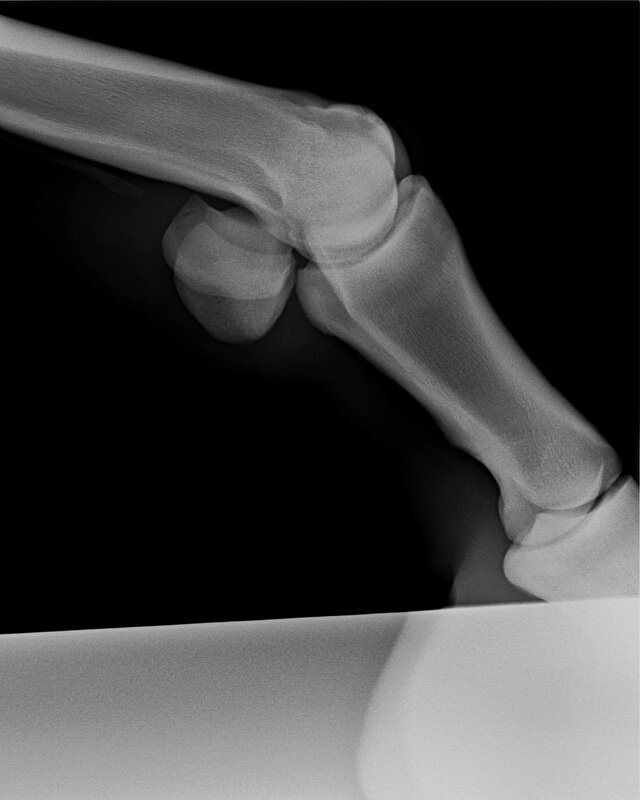

Mijn paard had ook al wat schade in het gewricht. Gedurende de operatie (mijn dochter was erbij) leek dat best groot gezien de krassen die te zien waren) maar in de praktijk viel dat reuze mee. Tijdens de operatie is dat via de camera natuurlijk erg uitvergroot. De chip was ook maar klein. Normaal gesproken, bij een chipoperatie, nemen ze middels een kijkoperatie het chipje weg (arthrectomie). Dit is een vrij standaard en simpele operatie. Paarden zijn dan ook weer snel op de been. Inderdaad met een week of 6 is het dan wel klaar. Mijn paard loopt dermate goed, dat een PRP behandeling niet nodig was.

Ik heb de indruk dat het botfragment bij het paard van TS dus vrij groot was. Gezien men ook het bot heeft moeten vlakken. Dan is de schade in het gewricht ook groter. Mogelijk zo groot dat geen herstel meer mogelijk is. Hoe lang je het paard ook rust geeft. Ik kan me niet precies visualiseren hoe het bij haar paard precies zit, maar dit is wat ik ervan weet.